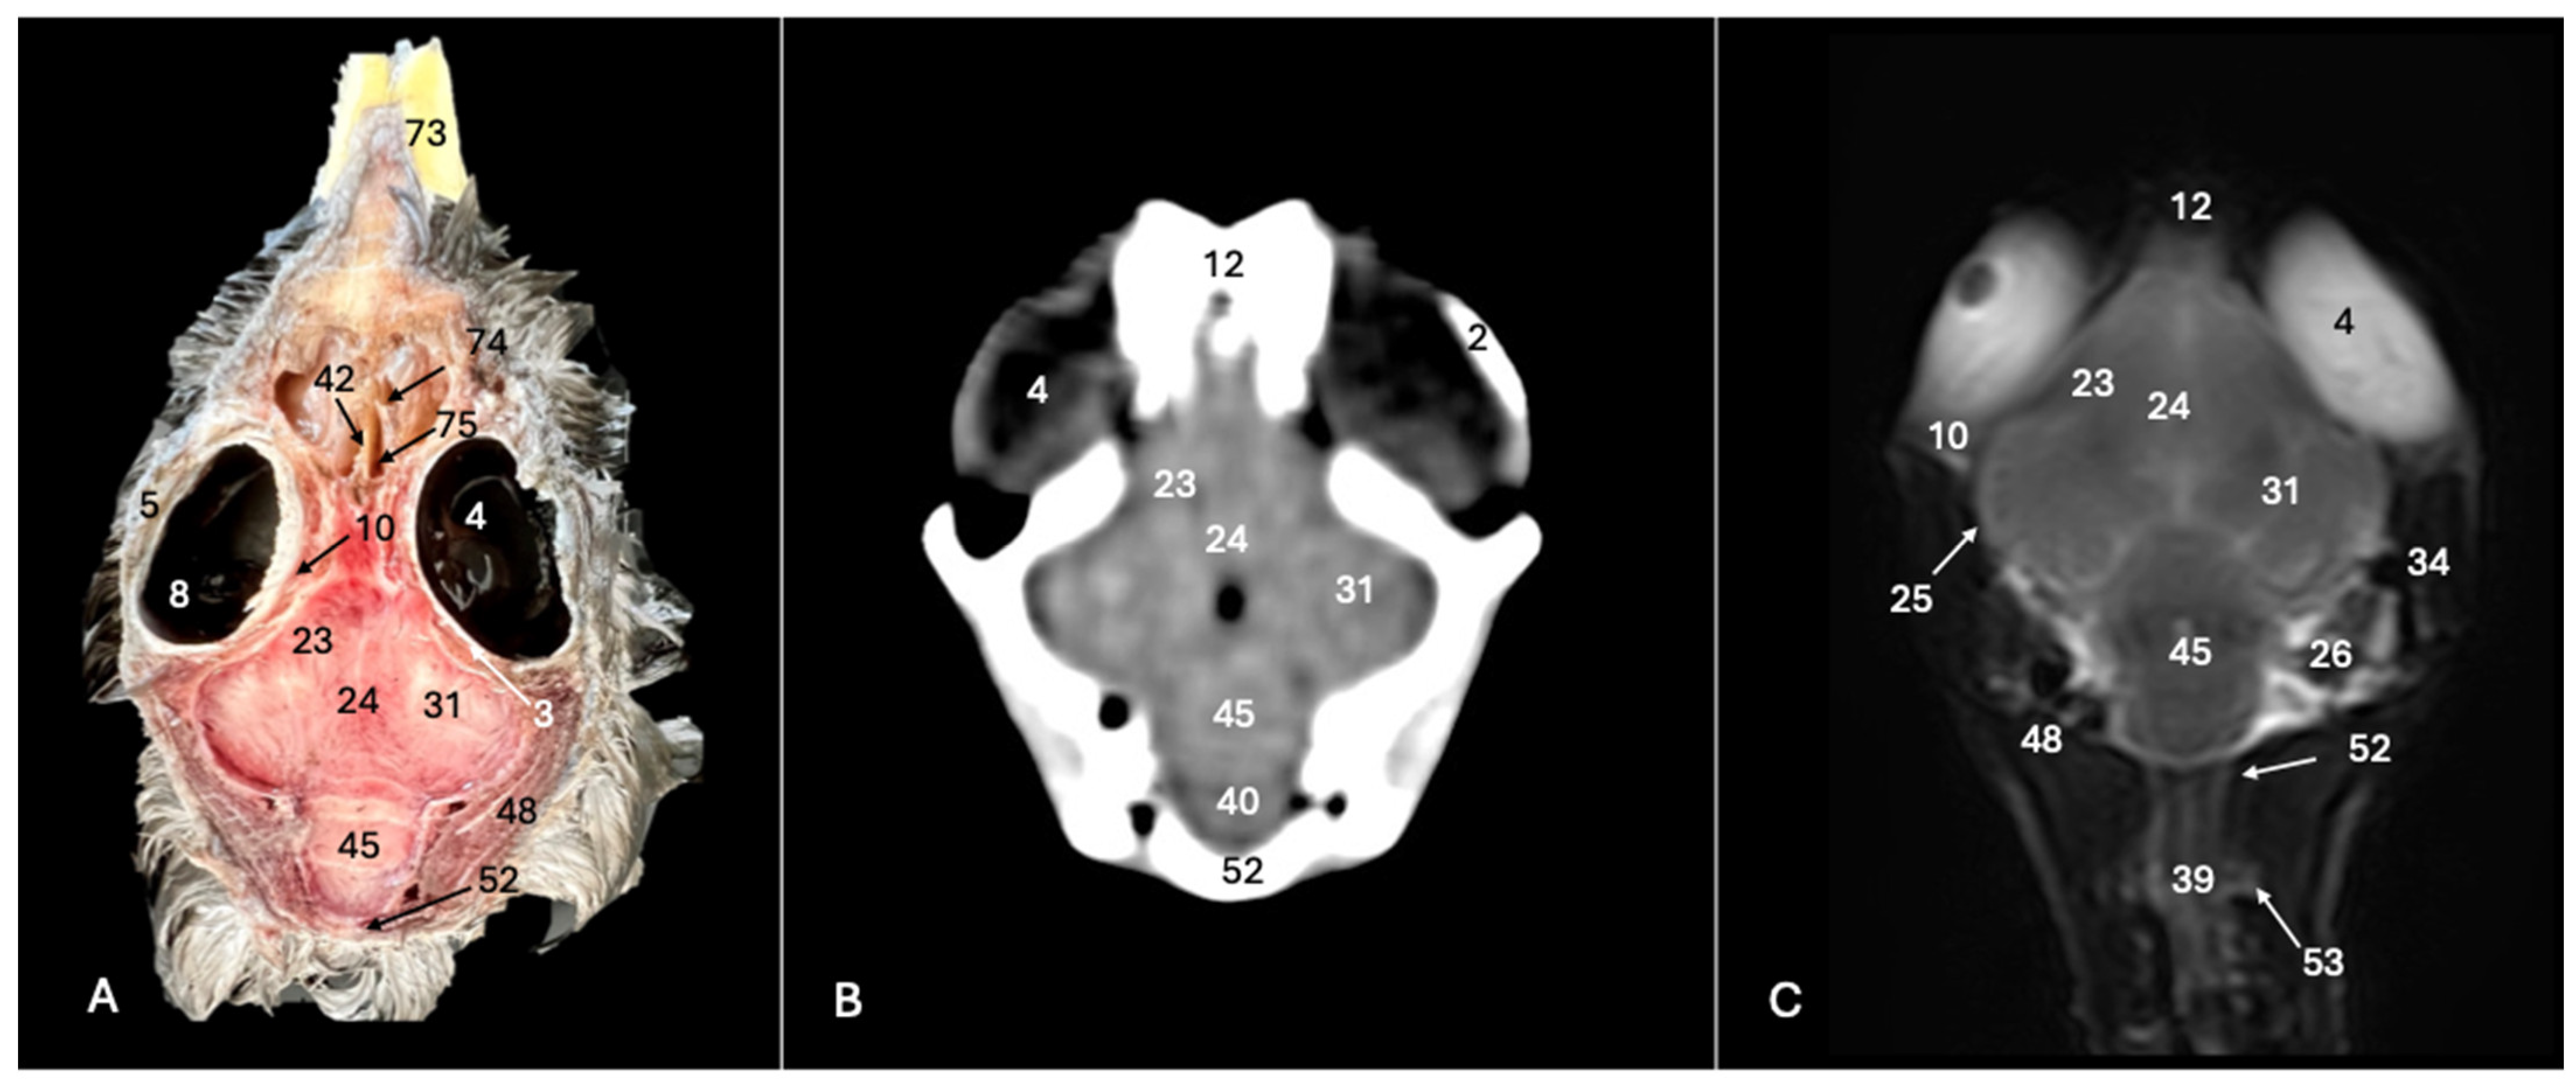

3. Result

3.1. Anatomical Sections

3.2. Computed Tomography (CT)

3.3. Magnetic Resonance Imaging (MRI)